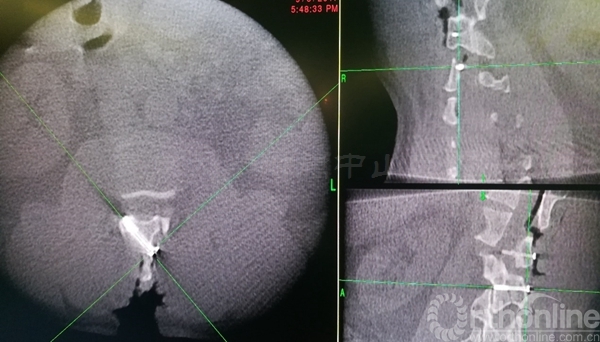

术中椎板截骨行肿瘤切除后,椎板回植术,回植椎板采用空心螺钉固定

术后肌力恢复至4+级,无脑脊液漏,X线片及CT平扫显示椎板回植位置满意,空心钉固定牢靠。术后病理诊断为脊膜瘤伴细胞丰富